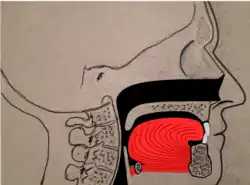

Genioglossus advancement

Genioglossus advancement (GA) also known as genial tubercle advancement (GTA), is a procedure that pulls the base of the tongue forward, usually to increase airway size due to deformity or a sleep breathing disorder. This procedure is frequently performed with either uvulopalatopharyngoplasty or maxillomandibular advancement surgeries.

Tongue muscles (genioglossus, geniohyoid and others) are attached to the lower jaw below the teeth. During a genioglossus advancement procedure, the surgeon cuts a small window or bone cut in the front part of the lower jaw (mandible) at the level of the geniotubercle where the genioglossus muscle attaches. This piece of bone, along with the attachment for the tongue (genial tubercle) is pulled forward and subsequently secured to the lower jaw, usually with a single screw or with a plate and screws.

This procedure is often combined with other surgeries such as uvulopalatopharyngoplasties or maxillomandibular advancement surgeries. It is rare to have this procedure performed as the only surgical treatment for sleep apnea, as obstruction in sleep apnea is most often at multiple levels (nose, palate, tongue, etc.).